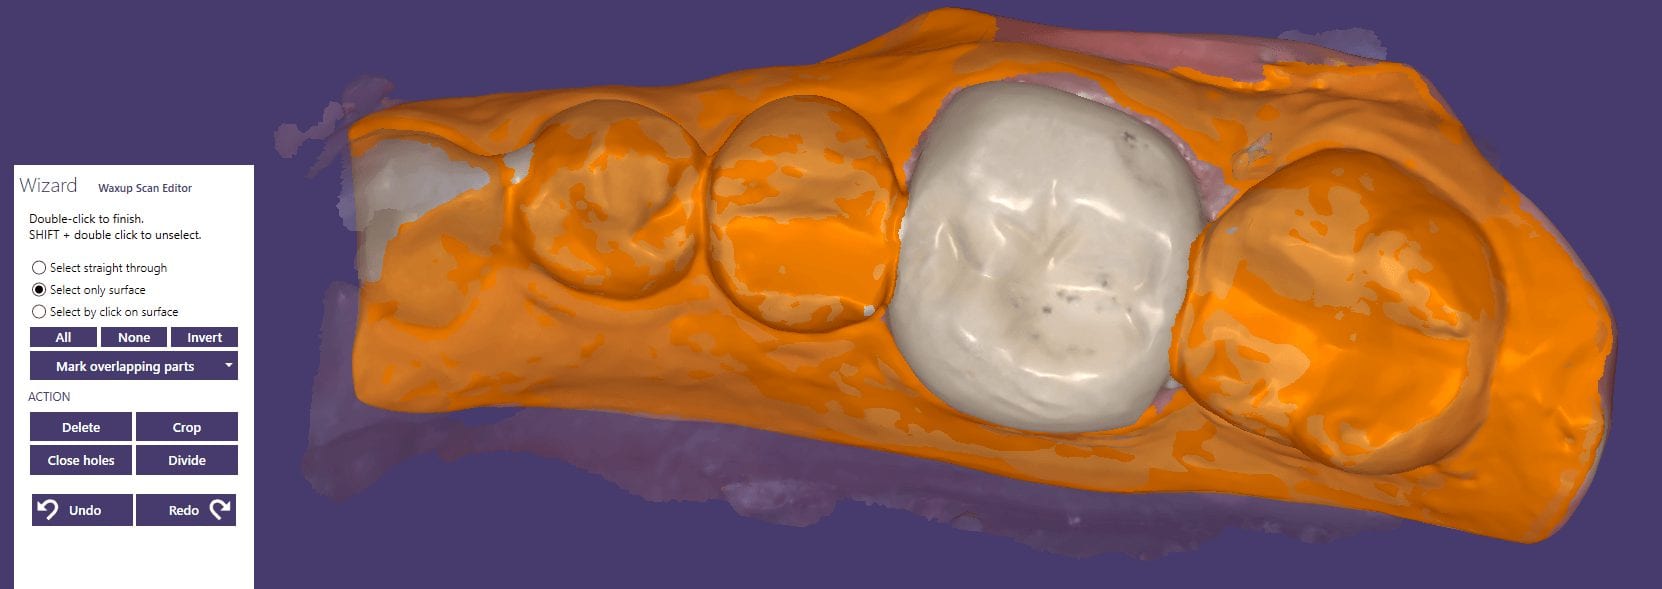

May 29, 2019A friendly reminder- this case was table top scanned with a desktop scanner so don’t get distracted, but be aware that for oral appliances, particularly for apnea treatment or bruxism, […]